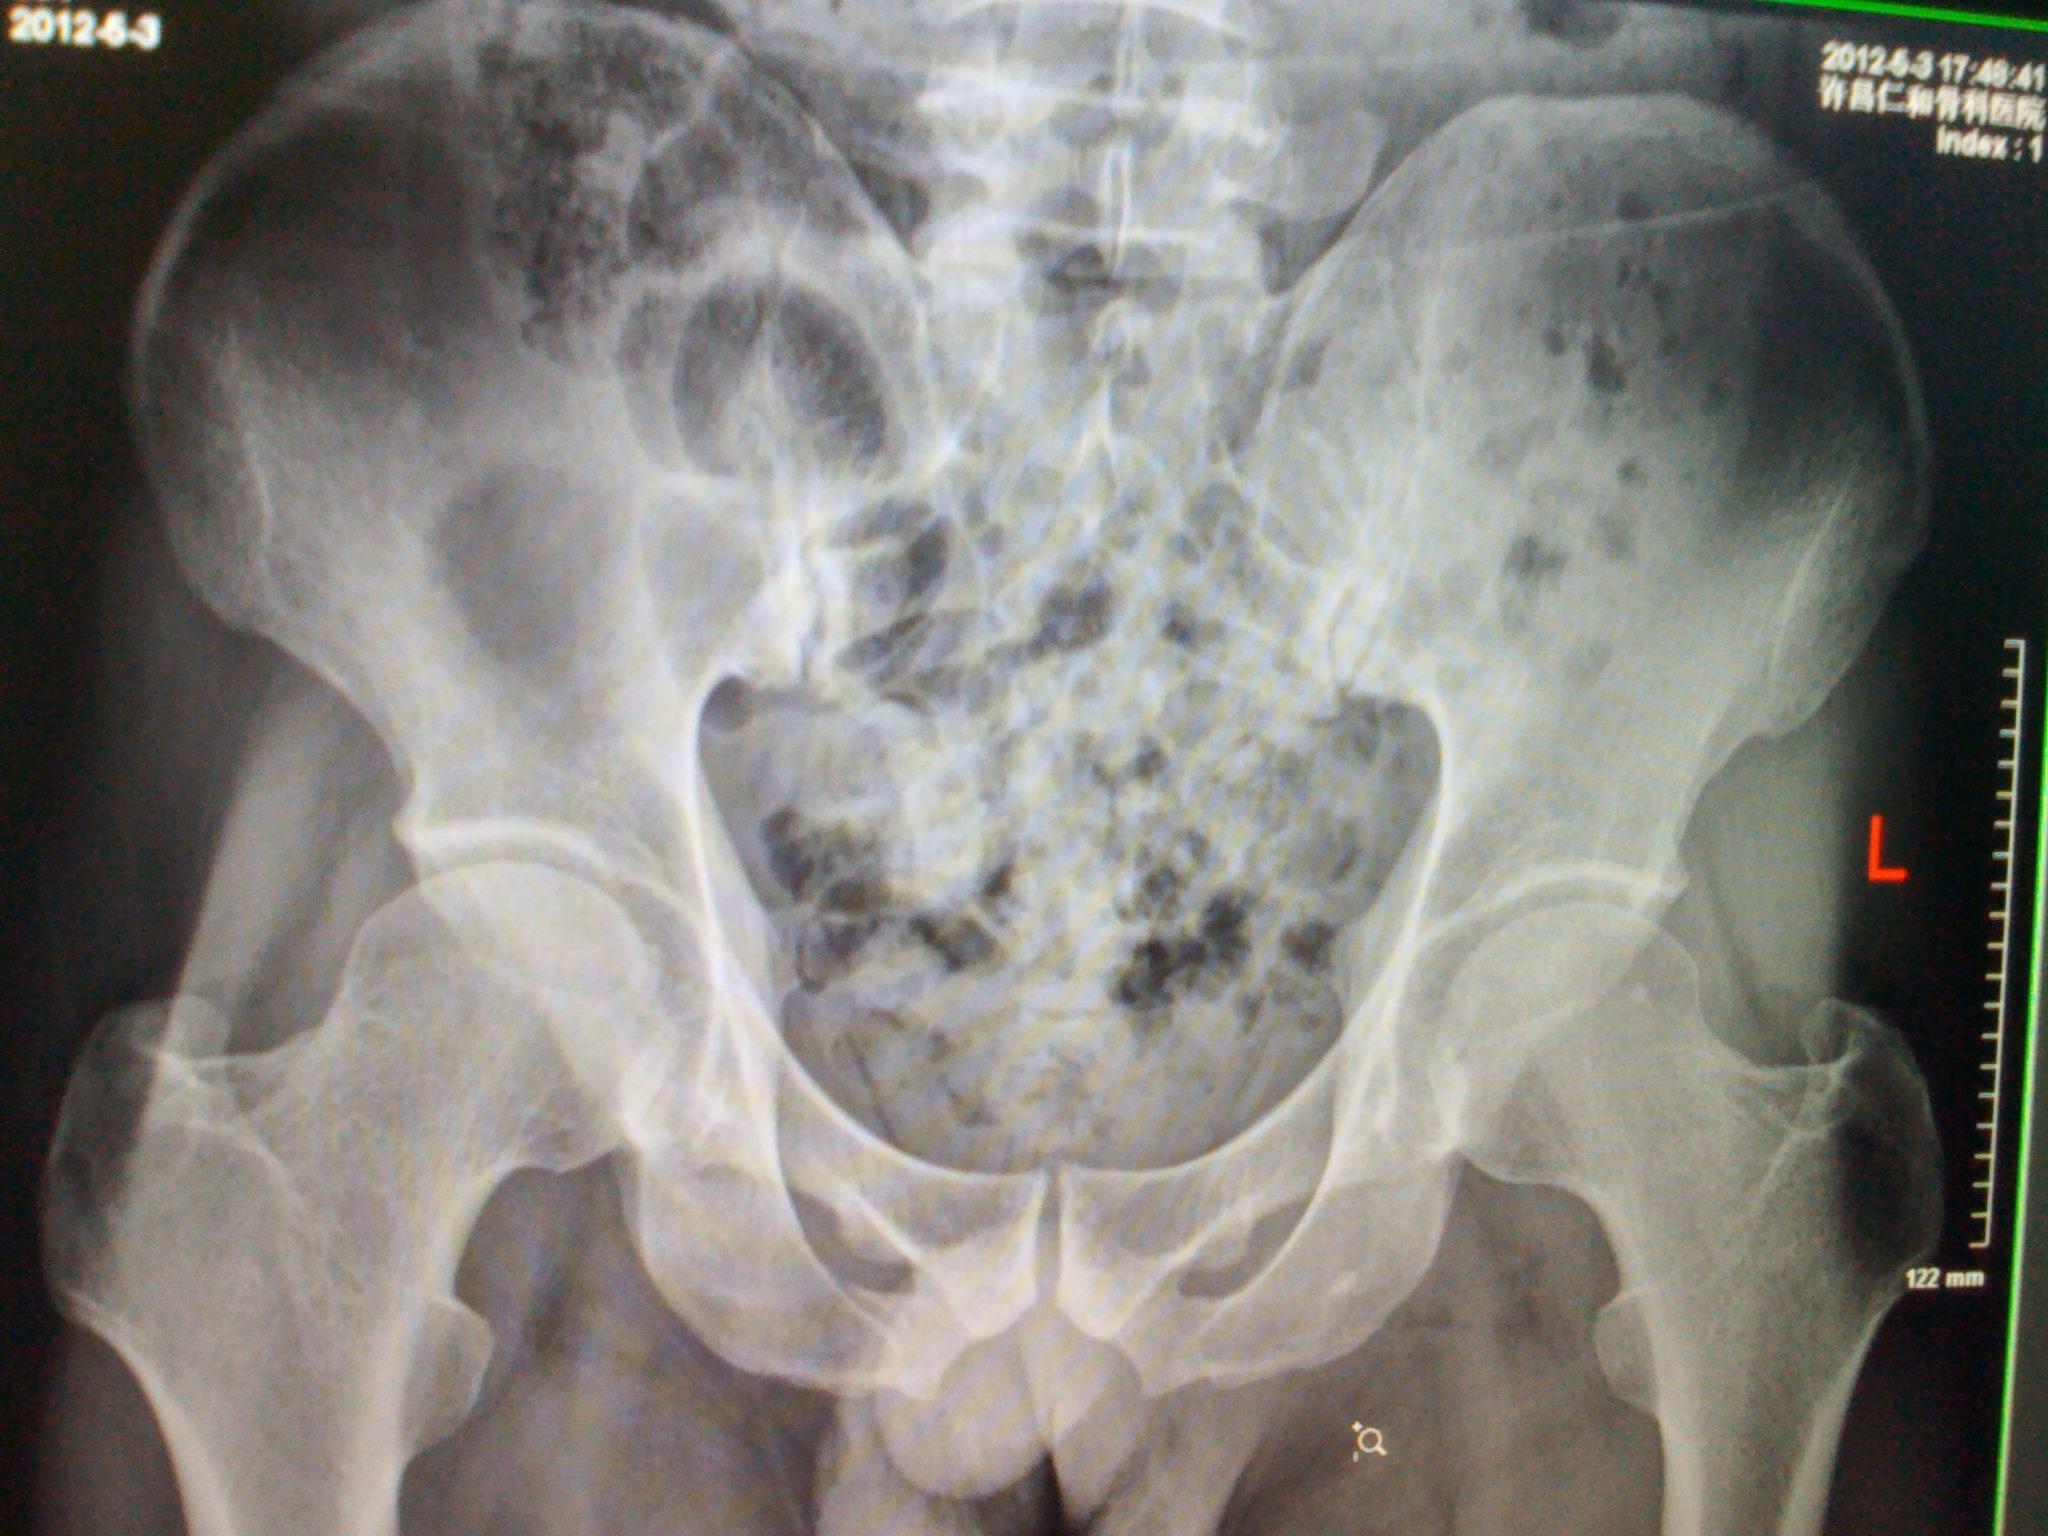

术前骨盆ct重建正位

疼痛伴活动受限1小时入院,入院后行骨盆x线片,骨盆ct及三维重建提示

疼痛入院,泌尿系b超未见明显异常,拍胸片,骨盆平片及骨盆ct发现病灶